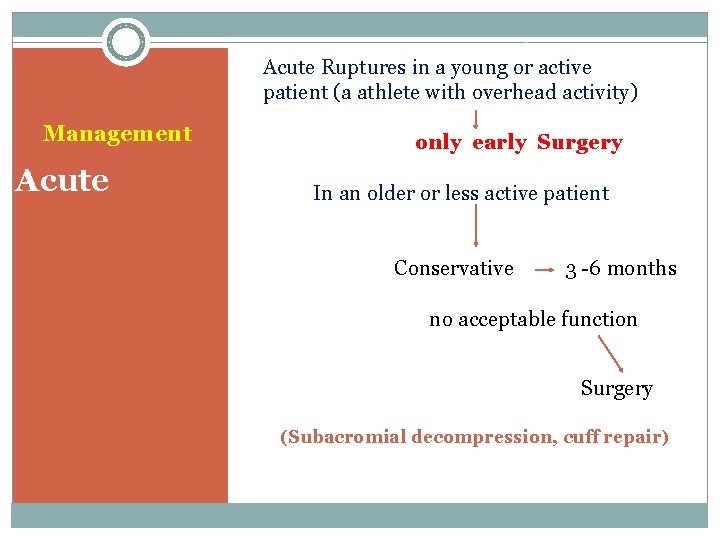

Acute Ruptures in a young or active patient (a athlete with overhead activity) Management Acute only early Surgery In an older or less active patient Conservative 3 -6 months no acceptable function Surgery (Subacromial decompression, cuff repair)

Treatment is conservative Treatment Surgery: Chronic 1. young patients with massive tearing and weakness 2. Old patients with sever pain that don’t control 3. RC tearing +biceps tendon tearing Response to conservative treatment (90% )